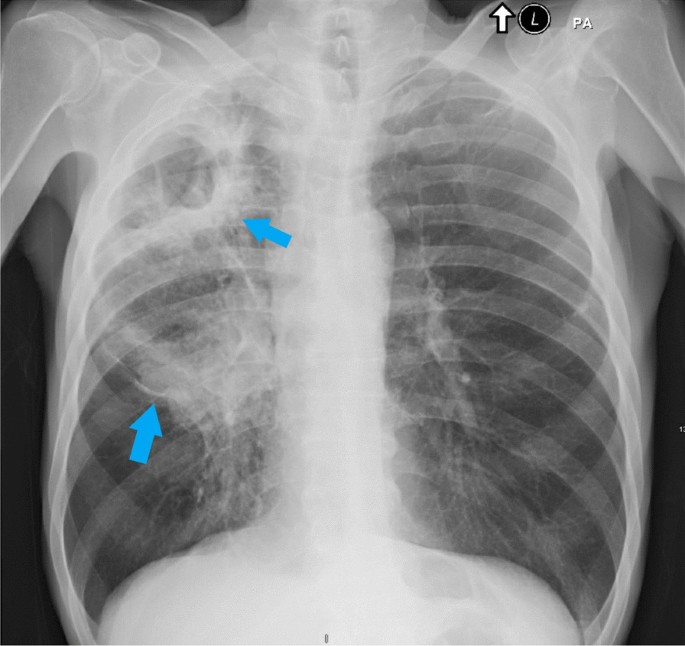

Lung Cancer

Lung Cancer Type Radiological Features

Non–small cell lung cancer (NSCLC) Solitary nodule or mass, irregular/spiculated margins, possible cavitation.

Small cell lung cancer (SCLC) Central or hilar mass, rapid growth, prominent lymphadenopathy.

Adenocarcinoma Peripheral nodule, sometimes ground-glass opacity or lepidic growth pattern.

Squamous cell carcinoma Central mass or nodule, frequent cavitation, hilar lymphadenopathy.

Large cell carcinoma Peripheral or central mass, rapid growth, may cavitate.

Bronchial carcinoid tumour Well-defined, round/oval nodule; central or peripheral; usually slow-growing.

Metastases to the lung Multiple nodules of varying size, well-defined margins, random distribution; may cavitate depending on primary.

Non–small cell lung cancer

Non–small cell lung cancer (NSCLC)

Small cell lung cancer

Small cell lung cancer (SCLC)